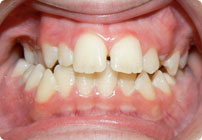

Caso: 19 años

Adulto: Clase III

Mordida Abierta Anterior

Mordida Cruzada Anterior y Posterior

Endo necesitado para #19

Extract U5’s, LR4, LL6

6 alambres superiores

5 alambres inferiores

Elásticos Clase III 2oz. TP Verde

Retenedores: Interior Fijo de TMA y Hawley en superior

Tiempo de tratamiento: 21 Visitas